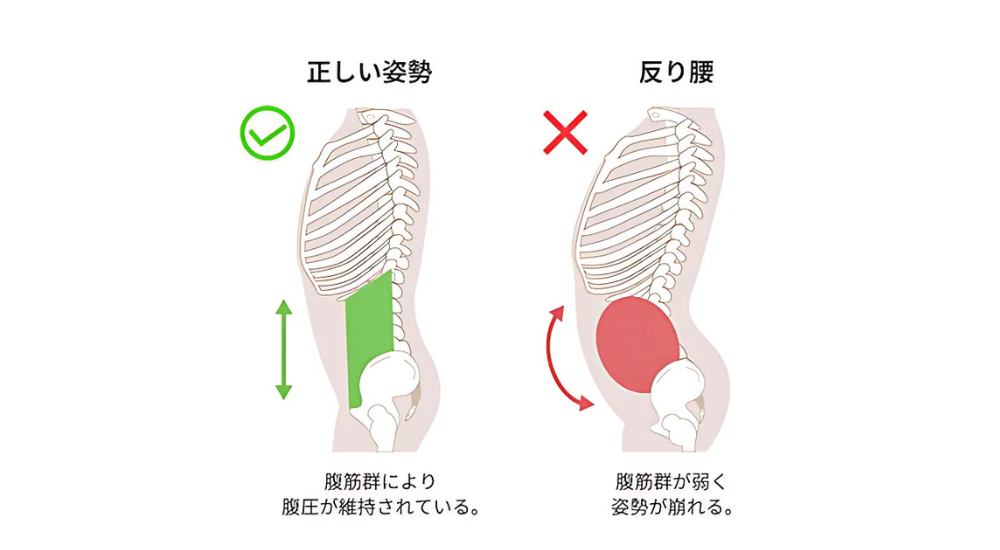

反り腰

腰の骨(腰椎)のカーブが強くなりすぎ、お腹を突き出し、お尻が後ろに突き出たように見える状態です。

原因: 骨盤の過度な前傾が主な原因です。長時間座る姿勢による股関節前面の筋肉(大腰筋など)の短縮・硬化、腹筋や大臀筋といった体幹やお尻の筋肉の弱化、ハイヒールの常用、妊娠による体型の変化などが挙げられます。

これらの要因により骨盤が前方に傾き、バランスを取るために腰椎のカーブが強くなってしまいます。

- 大腰筋・腸骨筋(腸腰筋): 腰椎から股関節前面にかけての筋肉。長時間座る姿勢で短縮・硬化しやすく、骨盤を前傾させ、反り腰を助長し、腰痛の原因となります。

- 脊柱起立筋(特に腰部): 腰の背骨に沿った筋肉。反り腰で常に緊張・短縮しやすく、腰痛の大きな原因となります。

理由② “天然のコルセット”である「呼吸とインナーマッスル」を正常化するから

良い姿勢を「頑張って」維持しようとしていませんか?本当に姿勢を支えるのは、お腹の深層にあるインナーマッスルと、その働きと密接に関わる「呼吸(横隔膜の動き)」です。私たちは、呼吸の改善やコアコンディショニングを通して、この“天然のコルセット”を再起動させます。頑張らなくても、内側から身体を自然に支えられるようになり、疲れ知らずの美しい姿勢が手に入ります。